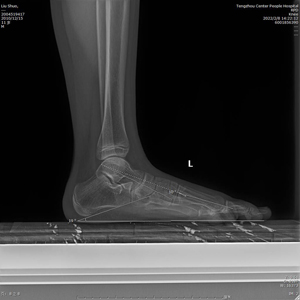

患者少年男性,11歲,因左足弓塌陷并內側疼痛不適1年收入院。張亞州、范明生主治醫師為患者完善術前檢查,嚴格術前查體,診斷為左足平足癥并左足副舟骨痛。

術前X線示:左足平足并副舟骨。患者經過足跟墊等保守治療效果不佳,潘維亮主任醫師主持全科醫護人員術前討論一致決定為患者實施全麻下距下關節制動術。